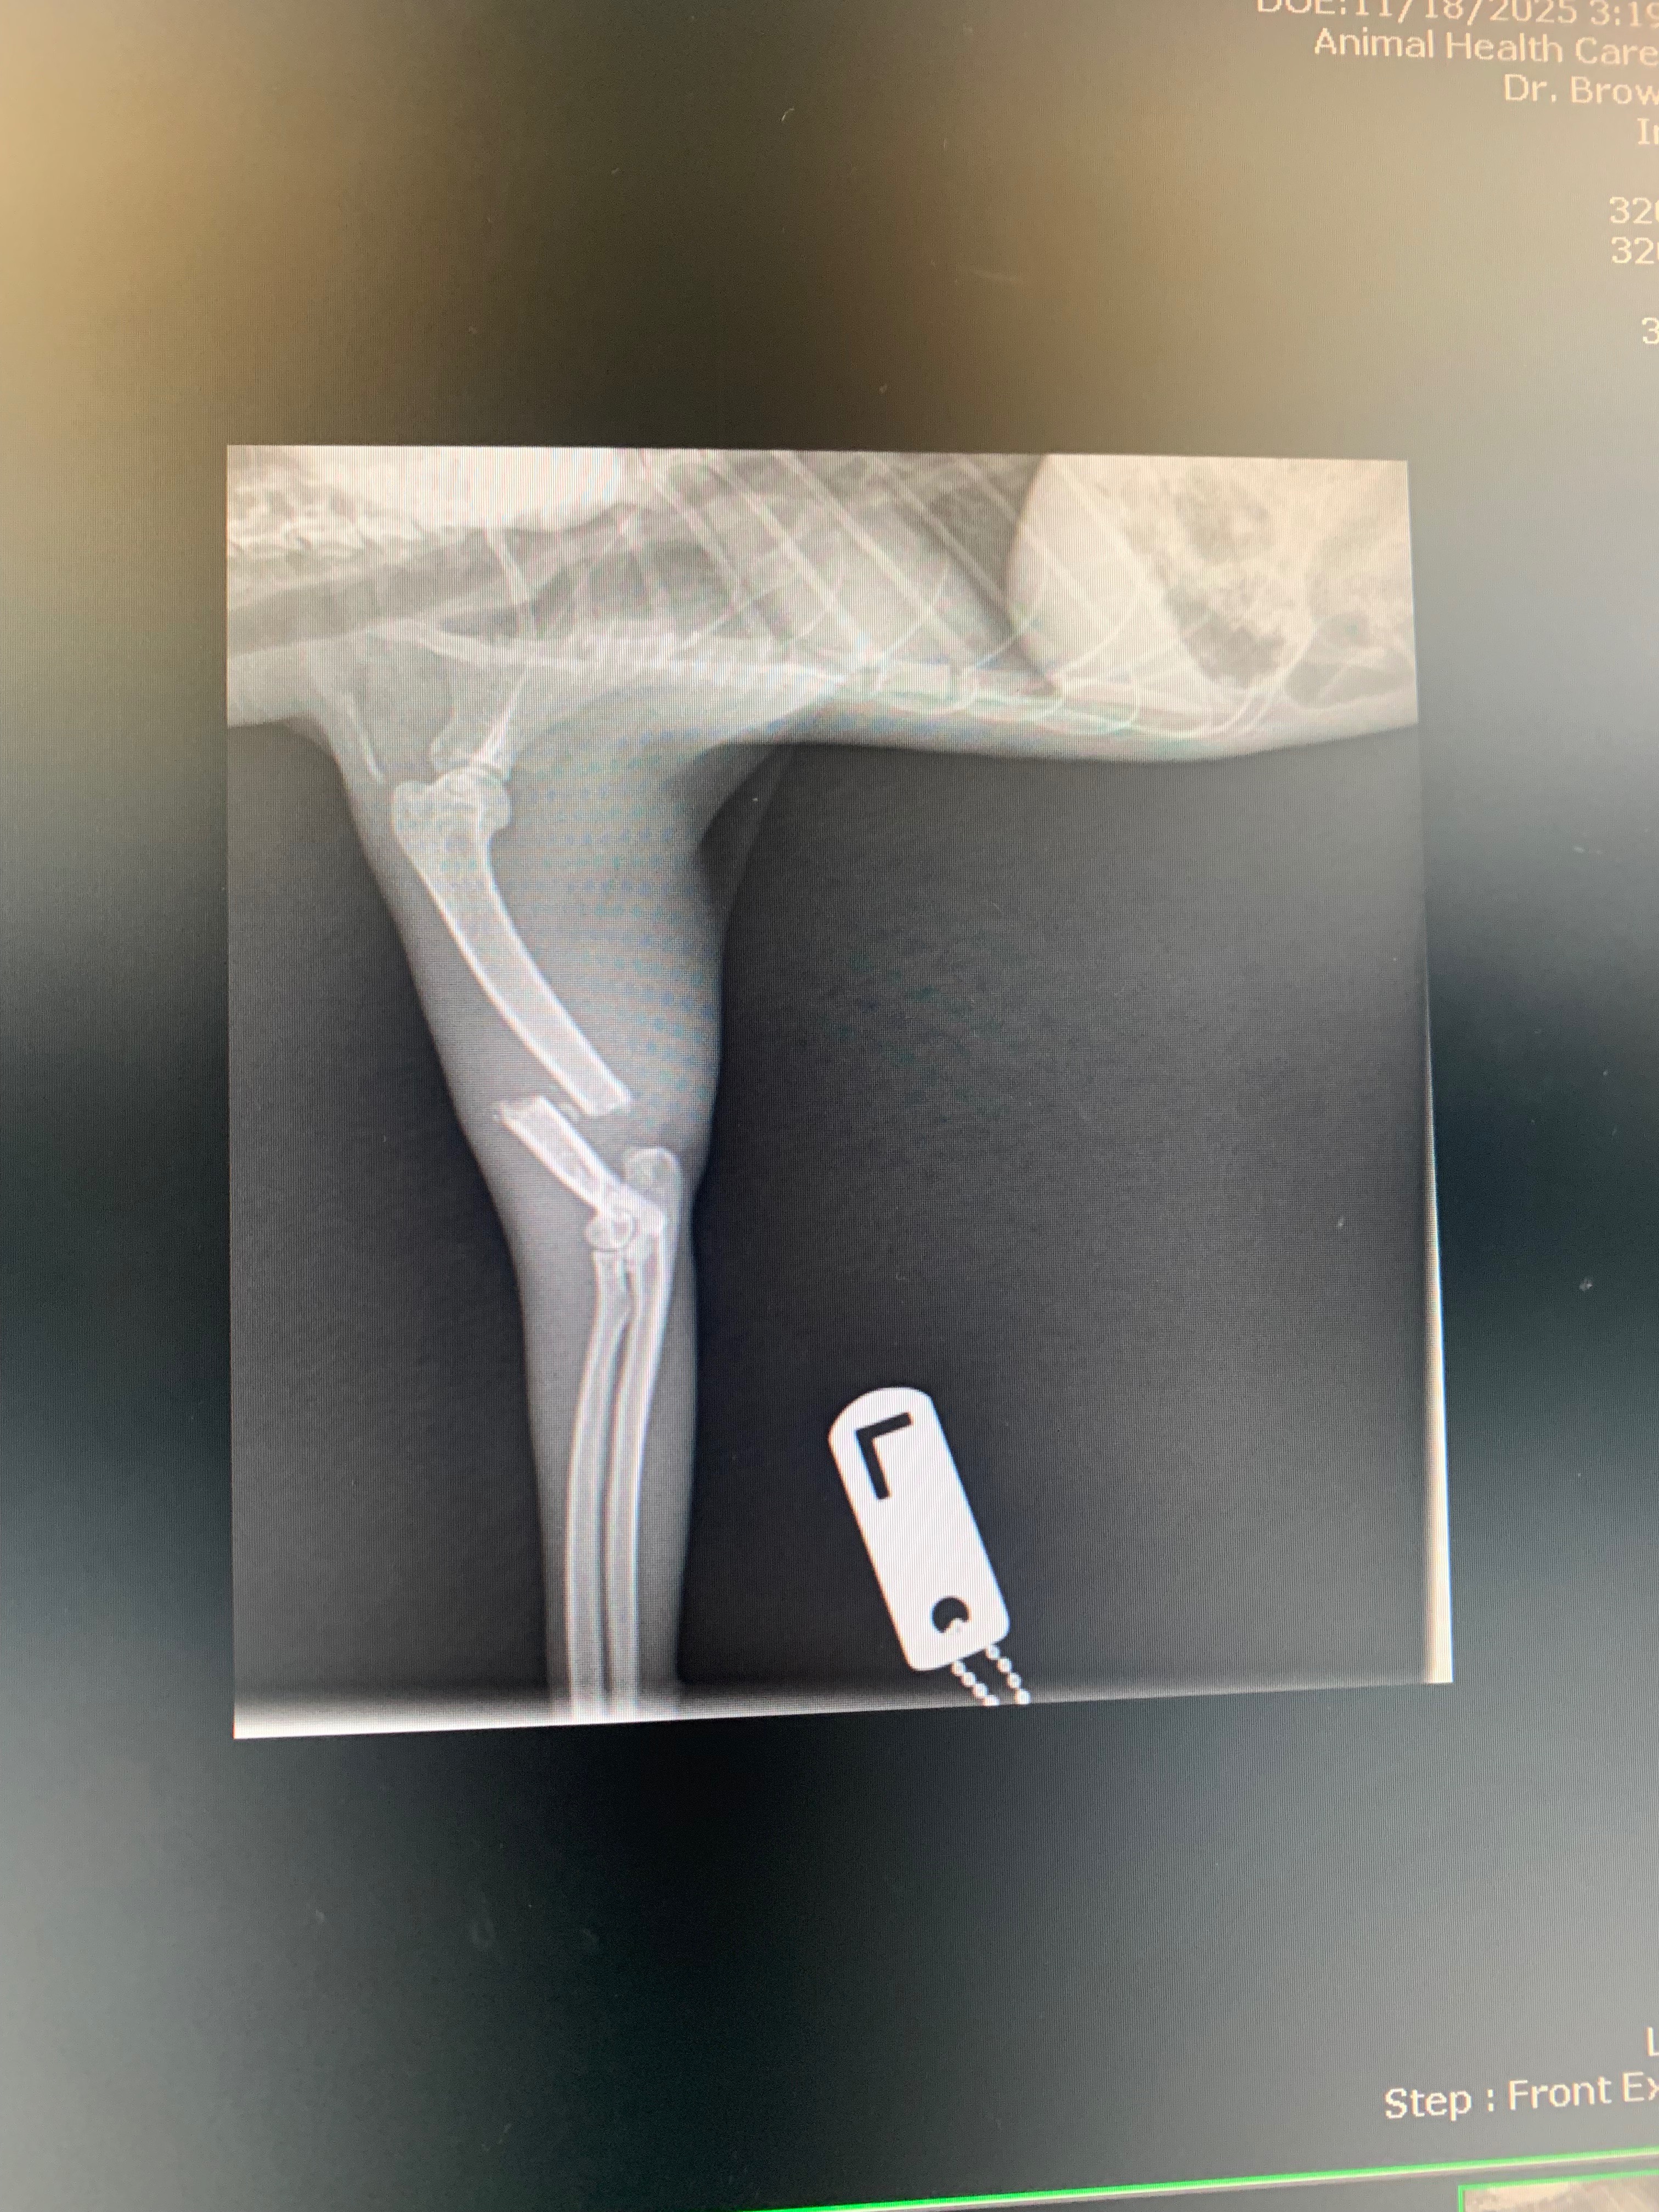

Michi is our beloved cat and a cherished member of our family. This morning, she was her usual playful self, but by early afternoon, we noticed something was terribly wrong. Michi was limping badly, her paw was sagging, and she couldn’t move it. To make things worse, her eye was bleeding a little. The wound wasn’t actively bleeding, but it was clear that she had just been hurt. We called our vet right away, and they were incredible—seeing Michi just 30 minutes after we called. After a quick diagnosis, we learned that Michi had broken her left leg very badly and would need surgery as soon as possible. We’ve scheduled her surgery for tomorrow morning, hoping to save her leg and get her back to her happy, healthy self. Michi is my first adopted stray baby, and it took a month to gain her trust. She’s always been our little shadow, following us around and bringing so much joy to our lives. She even brought her own babies to us, showing how much she trusts our family. Losing her would be heartbreaking, and we want to do everything we can to help her heal. The cost of her surgery and aftercare is overwhelming, and we’ve had to put it all on our credit card. We’re asking for help to pay off this bill so we can focus on Michi’s recovery and keep her safe and loved. Any support or shares would mean the world to us and to Michi. Thank you for reading her story and for caring about our sweet girl.